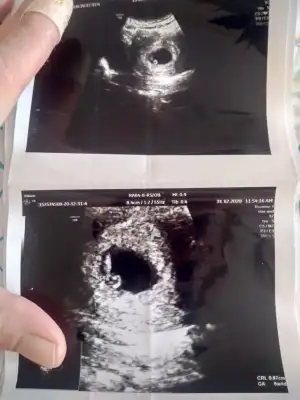

Kiz sankiCanım bana da bir tahminde bulunabilirmisin vajinal ultrason teşekkür ederim

Arkadaşlar cinsiyet tahmininde bulunablir misiniz vajinal ultrasonda çekildi